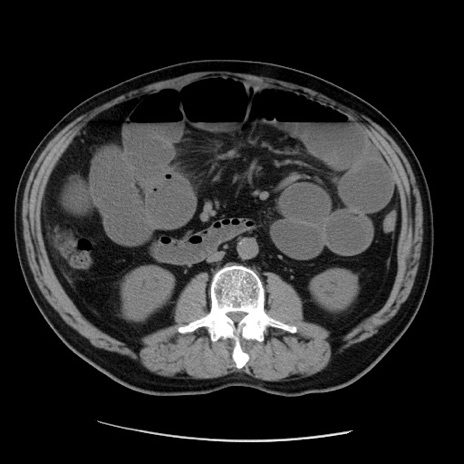

症例20(横断像)

【症例】 60歳代男性

【主訴】 腹部膨満、嘔吐

【現病歴】5日前頃より倦怠感を認め食事量減少し4日前の朝嘔吐、食事摂取困難となった。 3日前近医受診し点滴施行され整腸剤などを処方された。 当日他院を受診し、腹部膨満著明、炎症反応の上昇(CRP10.8、WBC11200)あり、紹介受診となる。

【身体所見】 意識JCS1 受け答えがはっきりしないBP 111/57mHg、 P 67bpm、、BT35.2°C、SpO2 97%(RA)、 腹部:膨隆、打診で鼓音あり、全体的に圧痛有り、腸蠕動音(-)、反跳痛ははっきりせず。

【データ】WBC 11400、CRP 14.20